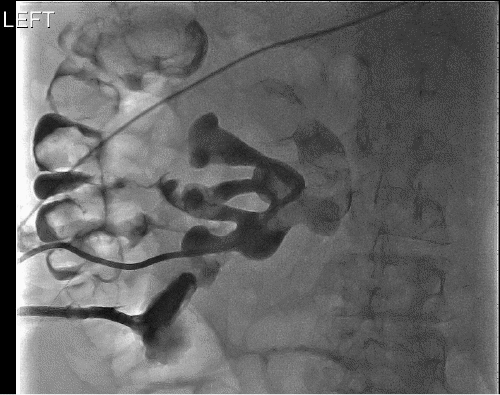

Figure 2. Intraoperative CT Images Showing Fistula, Renal Calculus, and Fungal Ball. Published with Permission

A) Immediate filling of fistula from left middle pole calyx into descending colon

B) filling defect in left upper pole calyx consistent with fungal ball or abscess ball